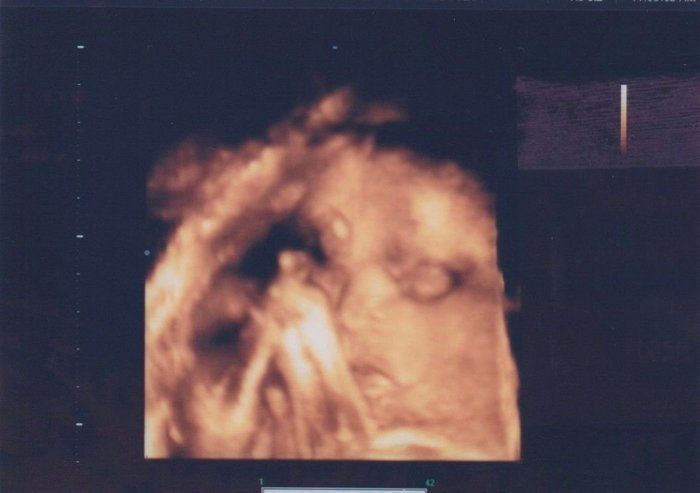

rainyさんの妊娠27週目のエコー写真 おなかがますます大きくなりました

おなかはもうすぐ100cmに達しそうです。おなかが大きすぎて腰痛が悪化し、立っているのがつらくなりました。赤ちゃんにまつ毛やまゆ毛が生えてくる時期だそうです。エコー写真は大仏様のような穏やかな顔に見え、3D画像は外人さんのように鼻が高く見えたので、どんなイケメンなのか、息子に会うのがとても楽しみになりました。赤ちゃんの推定体重は1324gでした。